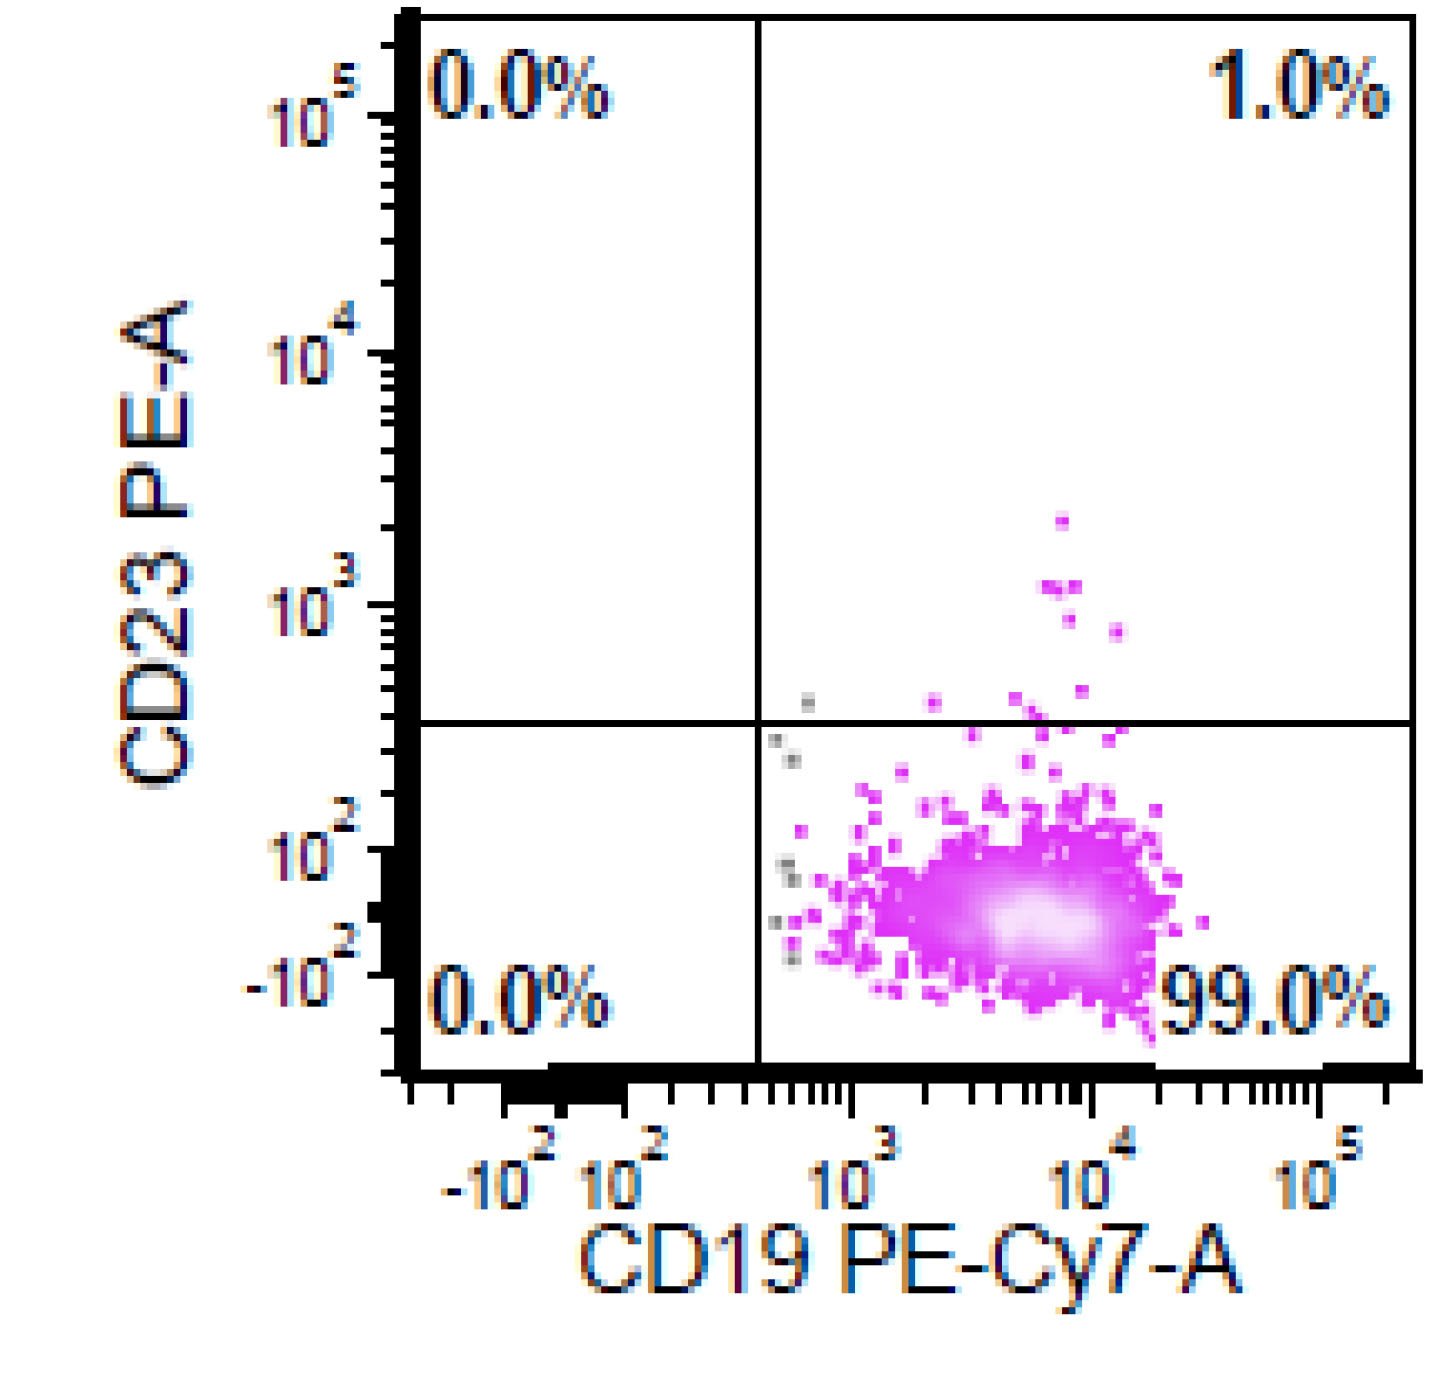

Flow cytometry description

- CD5+, CD19+, CD20+, CD22+, CD79b+, FMC7+

- Monotypic Ig (high level expression of surface light chains)

- CD11c variable, CD43 variable, CD200 variable

- CD3-, CD10-, CD23-

- Rare cases have atypical immunophenotype:

- CD5- or CD10+, CD200+ or CD23+ (dim ~10%)

Flow cytometry images

- This is the concurrent fine needle aspiration flow cytometry of the lymph node in a 70 year old man with lymphadenopathy. Cytology smears show intermediate to large lymphoid cells in a necrotic background. What is the most probable preliminary diagnosis before further work ups on the excised lymph node?

- Nodal marginal zone lymphoma

- Follicular lymphoma, grade 3A

- Mantle cell lymphoma

- Chronic lymphocytic lymphoma